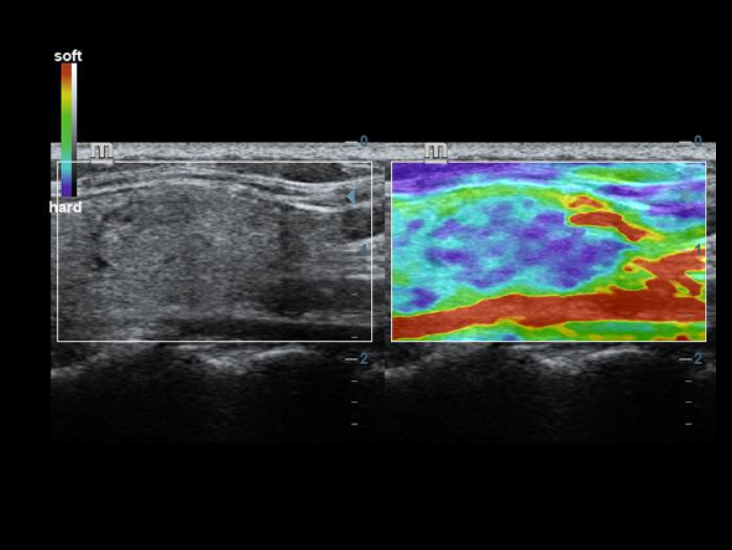

TecnologĂas de obtenciĂłn de imĂĄgenes clĂĄsicas: mejora de la calidad para el diagnĂłstico

Mediante la aplicaciĂłn de tecnologĂas de obtenciĂłn de imĂĄgenes clĂĄsicas, que se migran de sistemas de diagnĂłstico por ultrasonido consolidados, el DC-40 con Full HD le proporciona una mejor calidad de imagen con el grado de detalle que necesita.

- iClear (tĂ©cnica de imagenologĂa con supresiĂłn de manchas)

- PSHI (Phase Shift Harmonic Imaging)

- iBeam: tĂ©cnica de imagenologĂa de composiciĂłn espacial